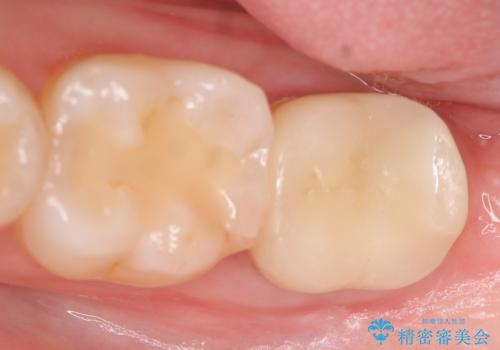

今回用いたオールセラミッククラウンはジルコニアフレームという白い素材の上にセラミックを盛っているため、審美性が非常に高いのが特徴です。

また、ジルコニアは人工ダイヤモンドの材料にも使われているほど高い強度を持っており、そのためオールセラミッククラウンは審美性だけでなく、奥歯やブリッジの補綴も可能とするクラウンです。